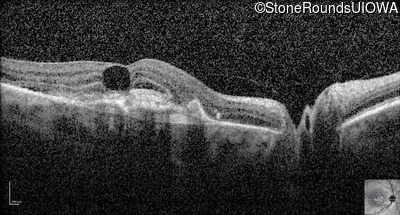

Optical Coherence Tomography - Right - 20/80 +1

Exemplar / OCT Stack